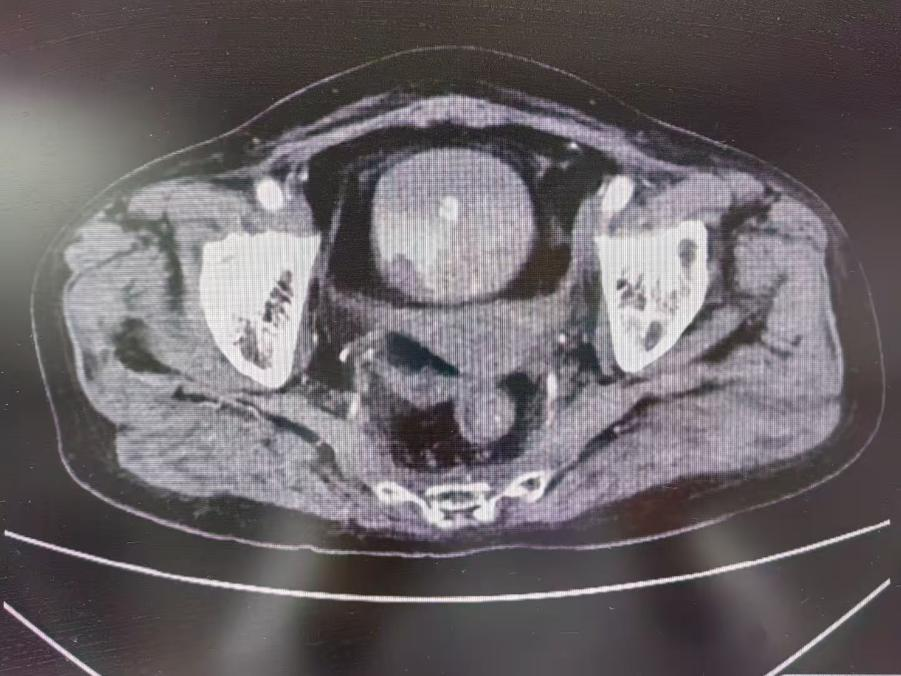

患者为老年女性,一年前因宫颈癌行同步放化疗及后装治疗。近2个月,患者出现持续血尿,血红蛋白低至44克/升,虽经多次输血支持,血红蛋白回升仍不理想。入院后,肿瘤科迅速启动多学科评估,协同介入团队为患者实施介入止血治疗,术后,患者尿液由红色转为清亮,活动性出血有效控制。